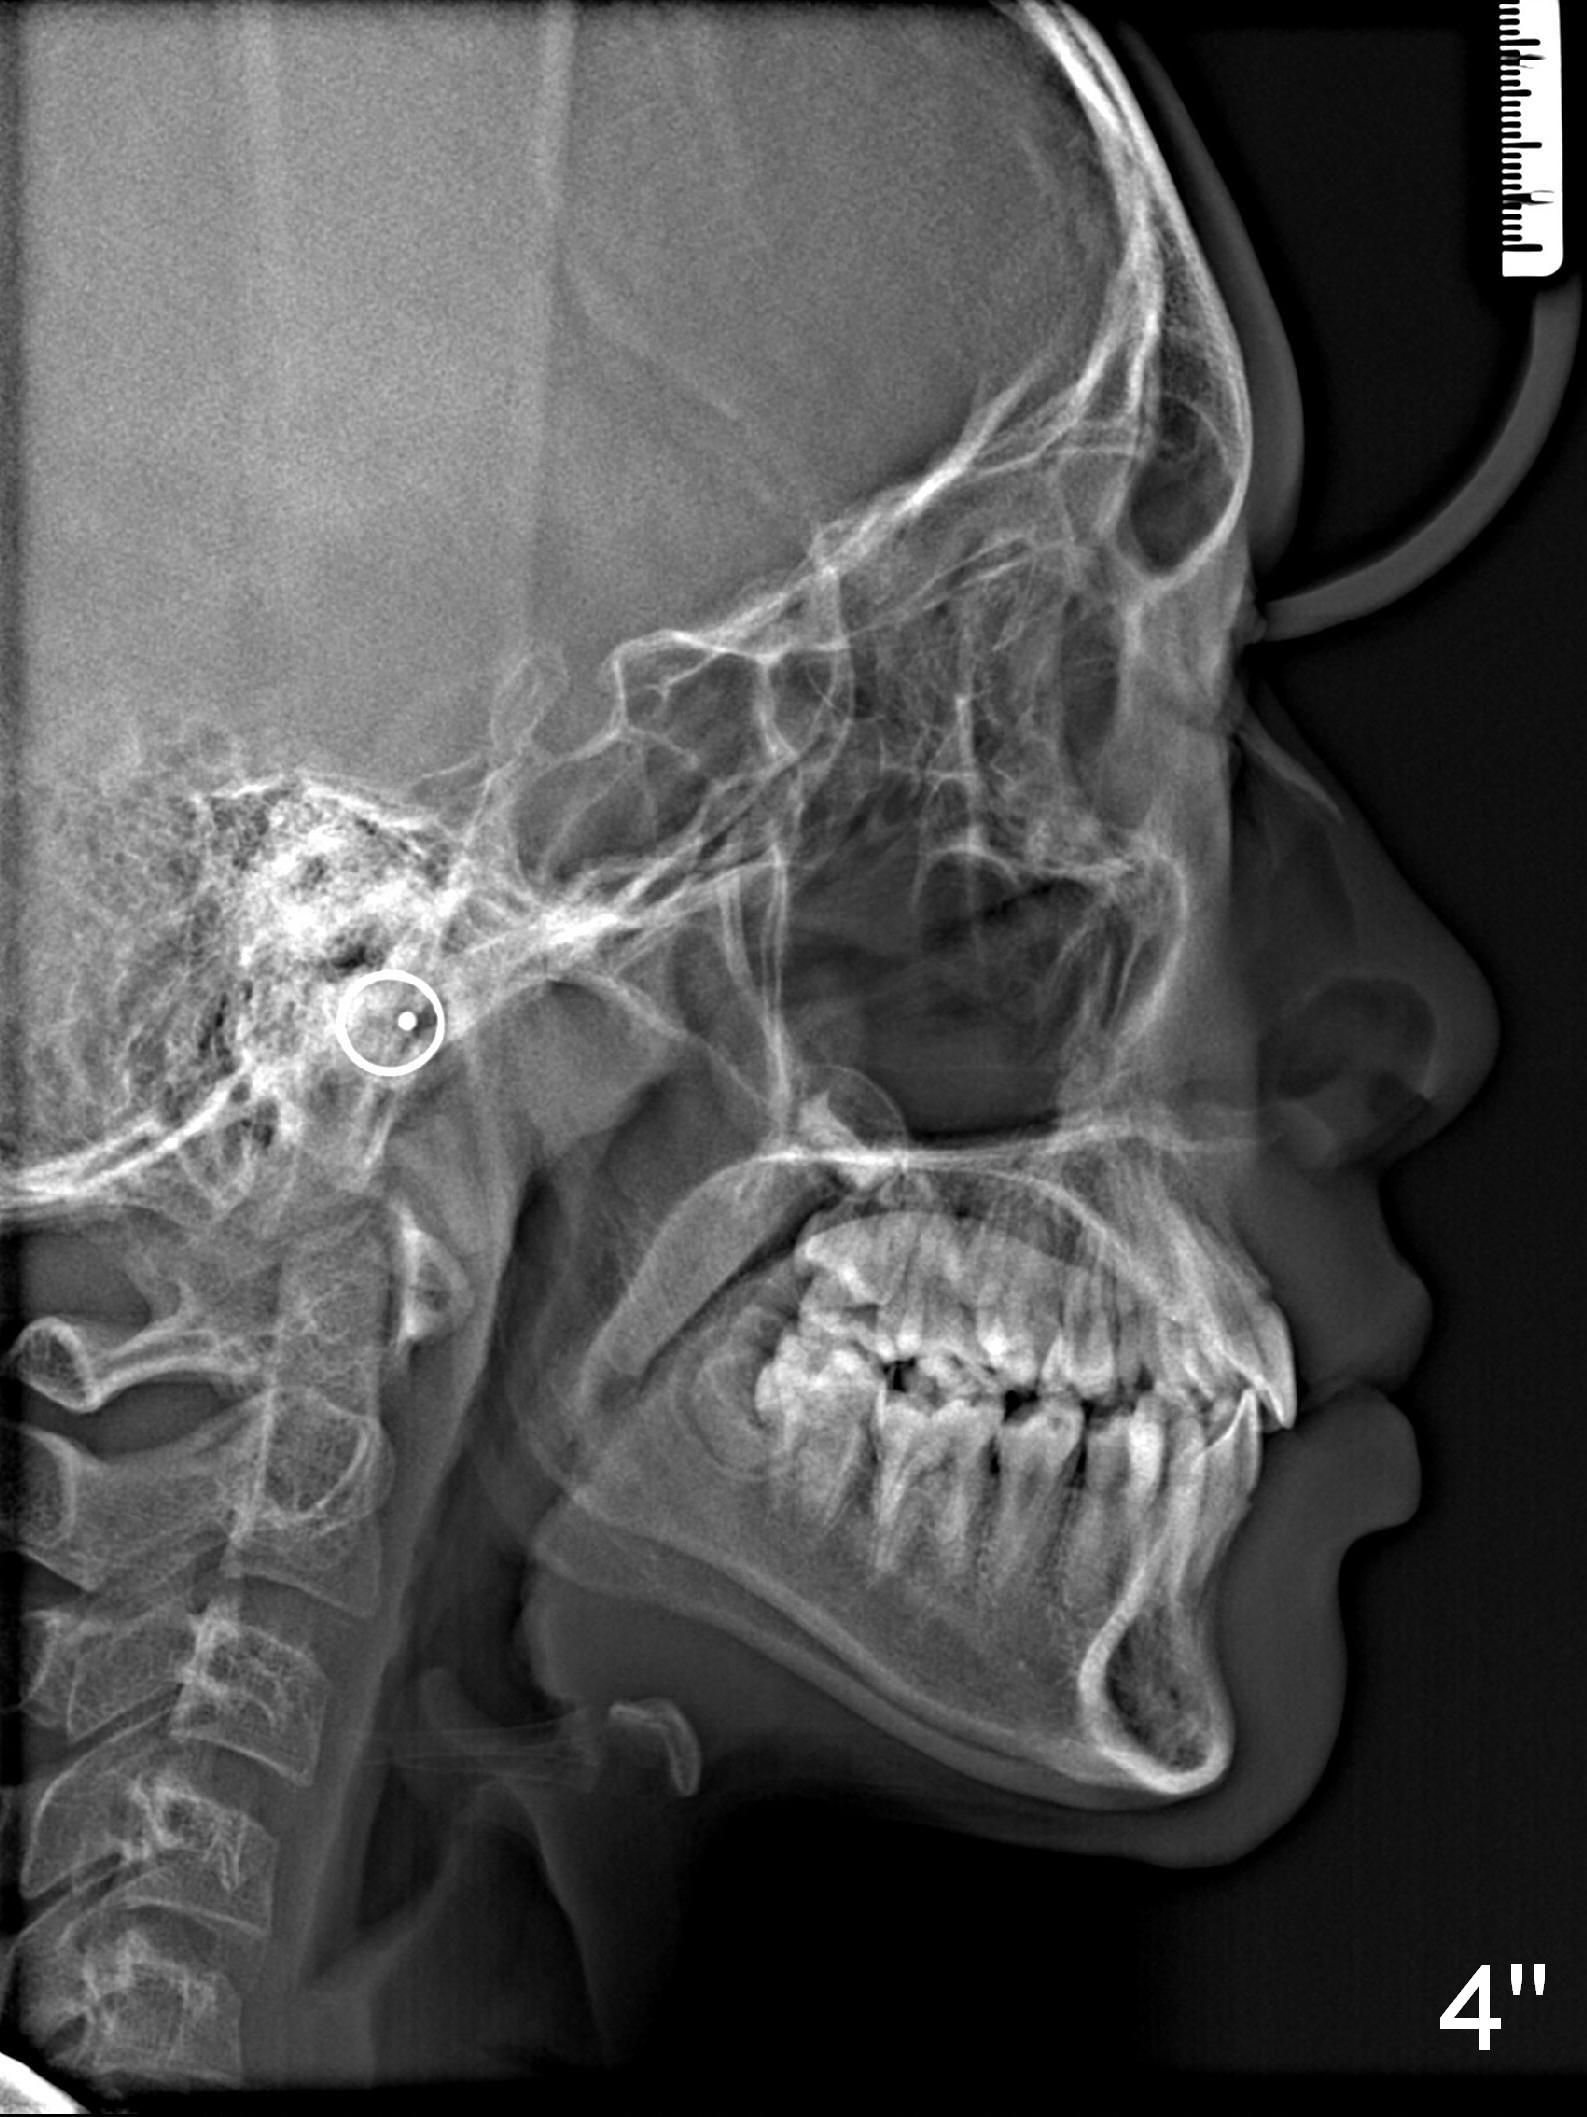

A 13-year-old man's malocclusion has two major components: upper midline deviation (Fig.2,5) and severe crowding (Fig.2,5-7).  His mother resists extraction, in spite of facial profile analysis (Fig.4,4').  A second obstacle to orthodontic treatment is his poor oral hygiene (Fig.5-7).  Before prophylaxis on Monday, can we decide together whether his oral hygiene has been improved drastically over the weekend?  If not, banding and bracketing will be canceled on Tuesday.

The advantage of extraction is that there is an opportunity to move the upper deviated midline to the right when UR4 space is available.

In addition to compromise of the facial profile, orthodontic treatment without extraction will move the roots of the anterior teeth out of their supporting alveolus.  There will be higher chance of the buccal gingival recession when he grows older.  Explain the above to his mother in layman's term.